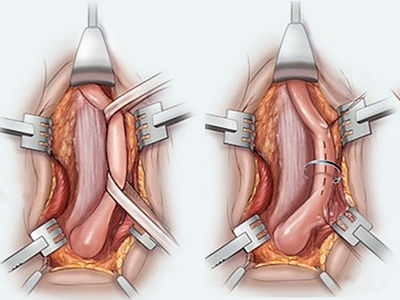

Ventral buccal mucosal urethroplasty

Notice: Trying to access array offset on value of type null in /home/u9176434/en.uretradarligi.com/wp-content/plugins/js_composer/include/autoload/vc-shortcode-autoloader.php on line 64 Notice: Trying to access array offset on value of type null in /home/u9176434/en.uretradarligi.com/wp-content/plugins/js_composer/include/autoload/vc-shortcode-autoloader.php on line 64 Notice: Trying to access array offset on value of type null in /home/u9176434/en.uretradarligi.com/wp-content/plugins/js_composer/include/autoload/vc-shortcode-autoloader.php on line 64 Ventral buccal mucosal urethroplasty ÖZGEÇMİŞ Yaş: 64…